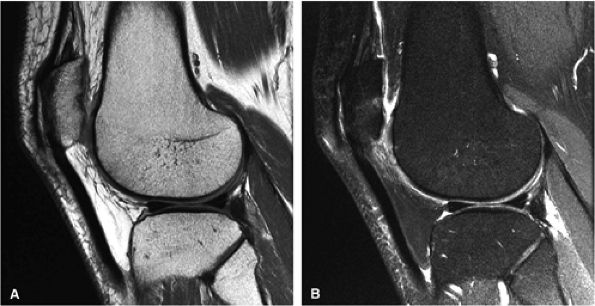

FIGURE 1.1 ● Routine knee examination. (A) Axial T1-weighted 2D fast/turbo spin-echo image. (B) Sagittal proton density-weighted image. (C) Sagittal proton density-weighted image with chemical fat suppression. (D) Gradient-echo image.

FIGURE 1.5 ● (A) PROPELLER fast spin-echo with a 480 × 480 matrix. (B) Conventional 2D fast spin-echo with 480 × 384 matrix. Scan times were identical. Note an apparent SNR gain in (A) as well as better delineation of cartilage and menisci.